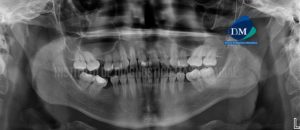

233 – Torus Palatino

Paciente femenino de 50 años de edad acude al Instituto de Diagnóstico Maxilofacial para evaluación imagenológica general debido a que se realizara un tratamiento de